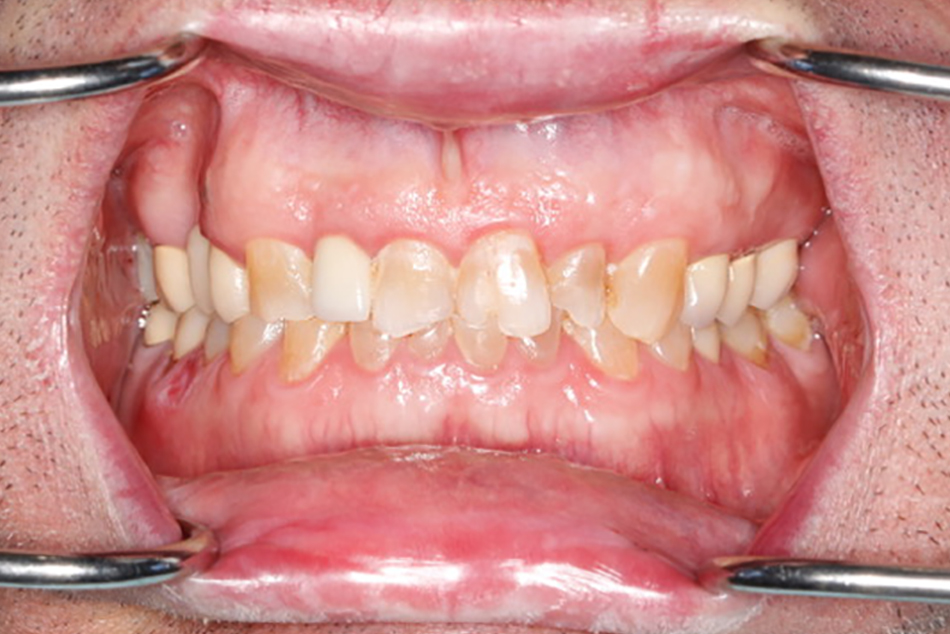

Patient 3 - Before

Full mouth restoration case before treatment